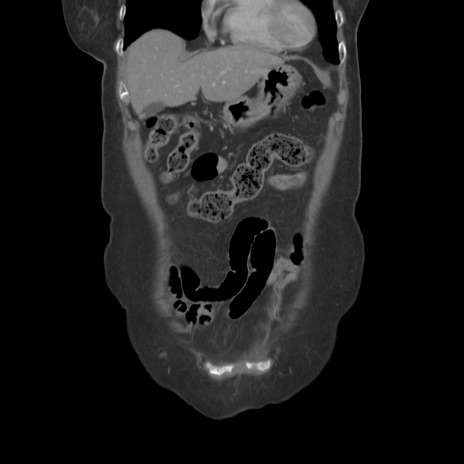

症例19(冠状断像)

【症例】80歳代女性

【主訴】下腹部痛

【現病歴】約8時間前より下腹部痛の出現あり、救急外来受診。

【既往歴】両側付属器切除

【身体所見】意識清明、下腹部正中に手術痕あり、その部位に一致して圧痛と反跳痛あり。腸蠕動音は亢進。

【データ】WBC 9300、CRP 0.15